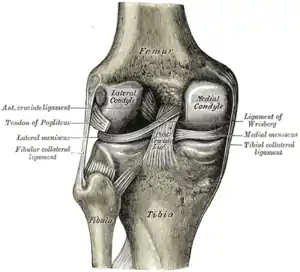

Cruciate ligaments

Left knee-joint from behind, showing interior ligaments.